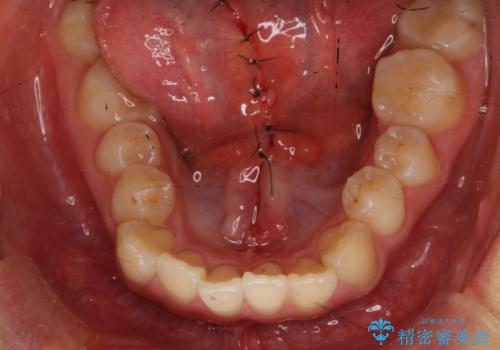

舌が持ち上がらない 舌小帯切除

- 舌小帯の切除を希望して来院。

術後に舌の運動(MFT)を行うことで、退縮の防止になります。

舌を持ち上げた時に、ハート型になるのが適応症です。